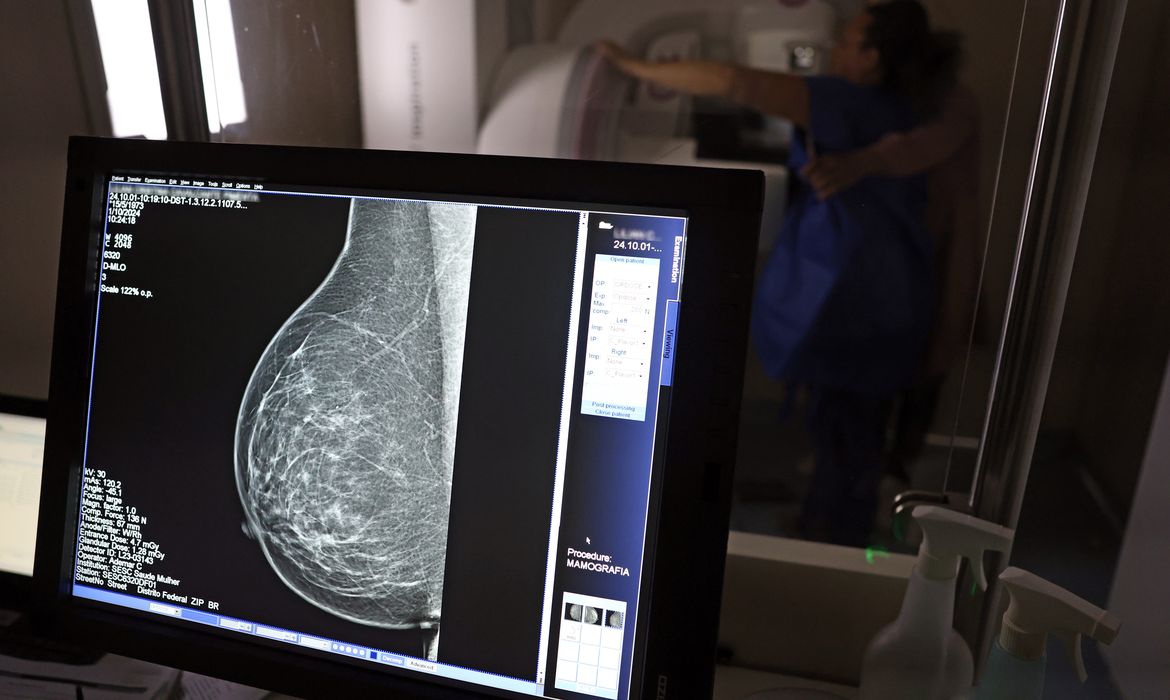

Ministério da Saúde passa a recomendar mamografia a partir dos 40 anos

Faixa de 40 a 49 anos concentra 23% dos casos de câncer de mama

O Ministério da Saúde passou a recomendar o acesso a mamografia, via Sistema Único de Saúde (SUS), para mulheres de 40 a 49 anos – mesmo que não haja sinais ou sintomas de câncer de mama. De acordo com a pasta, a faixa etária concentra 23% dos casos da doença, e a detecção precoce aumenta as chances de cura.

Até então, a orientação era que o exame fosse feito a partir dos 50 anos.